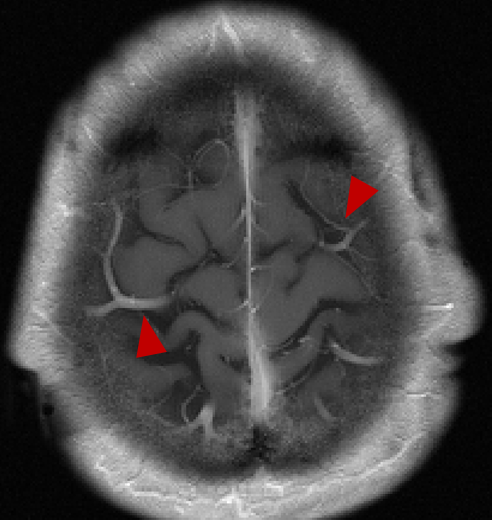

The reconstructed images from the learned trajectories using radial trajectory were demonstrated in Figure 4. These images were compared with the images directly reconstructed using fixed trajectory. The framework was slightly modified by removing the trajectory optimization network and only training the end-to-end reconstruction U-Net using the standard supervised learning approach. The qualitative evaluation of brain images proves the improved image reconstruction using our proposed method. As illustrated in Figure 4, the reconstructed images from learned trajectories are consistently better than those from the fixed trajectories for each type. More specifically, the learned radial trajectories provided improved reconstruction performance compared to their fixed counterparts in Figure 4 for the brain images at the AXT1POST sequence (More results in Appendix). Notably, the intermediate images directly obtained from the RSS reconstruction were shown at the top row of Figure 4 for the learned and fixed trajectories. It is evident that the learned trajectory can better remove structural and aliasing artifacts and provided more realistic image features and accurate image contrast than that of the fixed trajectory at the same level of acceleration, indicating the efficacy of the learning-based trajectory optimization.